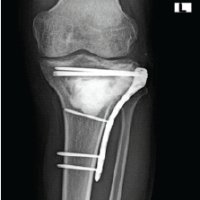

Radiographs of the knee revealed distal thigh subcutaneous and intramuscular emphysema (Fig. 3). MRI of the knee revealed a knee effusion, distal thigh fluid collections, and significant gas foci (Fig. 4). CT of the thigh also exhibited large multiseptated fluid collections in the anterior compartment of the thigh, gas to the level of the greater trochanter along fascial planes, a knee effusion, and diffuse soft-tissue edema (Fig. 5). LRINEC score was 9 [11-13]. The patient also complained of new-onset discomfort in the left shoulder and right posterior chest. A chest CT-scan revealed a gas-forming intramuscular abscess in his left infraspinatus muscle and a right posterior chest wall abscess without gas (Fig. 6).

During the procedure, an incision was made over the anterolateral knee in line with the previous lateral scope portal incision. Significant purulence and “dishwater” fluid were present (Fig. 7). The incision was carried to the level of the greater trochanter. Blunt dissection along the fascial planes of the thigh showed complete dissociation of the fascia from the subcutaneous tissue. A thorough debridement was completed throughout the anterior thigh (Fig. 8). The NF traveled along the fascial plane to the level of the hip joint and inguinal ligament. An arthrotomy of the knee joint revealed clear synovial fluid without intraarticular purulence. Approximately 500 mL of purulent fluid was evacuated from the thigh. The involved musculature appeared grossly viable. Upon completion of the I and D, an irrigating wound vacuum-assisted closure (WV) dressing was placed over the thigh dead space and along the surgical wound. The irrigating wound vacuum delivered acetic acid for 24 h followed by normal saline.

Day 29: The patient elected to undergo a repeat left thigh I and D and WV change. There was no evidence of muscle necrosis or purulence. Consequently, a regular WV was applied. All cultures from the thigh, shoulder, and chest wall again grew MSSA. The patient remained inpatient for 4 more days and received two bedside WV changes to the left thigh. Day 34: The patient refused further inpatient treatment and was discharged with home-health WV changes and IV antibiotics for 6 weeks. This was followed by a successful split-thickness skin graft (Fig. 9). Day 124: The patient continued to suffer from a persistent right chest wall gas-forming abscess. He received an additional IR-guided drain placement. Day 214: Persistent drainage from the wound forced an open I and D. The patient subsequently managed the wound with packing changes for 6 months before it healed by secondary intention. Although the patient’s posterior chest wall wound did not completely heal until 12 months after initial presentation, he was able to return to part-time employment at 3 months. And full-time employment at 5 months. His primary care provider and endocrinologist managed his diabetes with a combination of metformin and insulin. Aside from postoperative scar tissue formation, the patient states he has fully recovered, returned to all previous activities, and had no further necrotizing soft-tissue infections (Fig. 10).